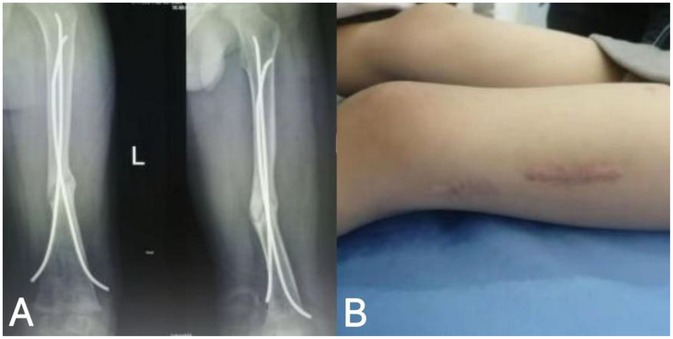

Figure 2. Imaging findings and local skin condition at the affected site prior to rESWT treatment in pediatric patients; (A) 9 months after fracture surgery; (B) localization of the left thigh of the child.

Physical examination revealed a 6-cm long healed surgical scar in the mid-thigh region of the left leg (Figure 2B), consistent with prior operative intervention for fracture management in the pediatric population. The local skin exhibited normal coloration without elevation in temperature, erythema, or exudation. Palpation demonstrated no significant tenderness; however, axial percussion elicited pain, potentially suggesting underlying complications such as delayed union or nonunion (22). Active range of motion (ROM) of the left knee joint was 0° (extension) to 120° (flexion), while the contralateral limb demonstrated a ROM of 0° to 135° (extension to flexion), indicating mild flexion restriction on the affected side, which may relate to impaired fracture healing or biomechanical factors (23). Muscle strength of the left lower limb, assessed using the Manual Muscle Testing (MMT) scale, was graded as 5 (normal). MMT is a validated method for evaluating muscle function by observing the strength, amplitude, and speed of contraction during active movement against resistance. During testing, the examiner instructed the patient to perform specific movements based on muscle group functions (e.g., knee extension and flexion for quadriceps and hamstrings) while applying appropriate resistance; the ability to resist was graded on a 0–5 scale, with grade 5 denoting full resistance against gravity and maximal force throughout the complete range of motion, signifying unimpaired strength (24). Additionally, superficial and deep sensations were intact, the dorsalis pedis artery pulse was strong, peripheral perfusion and skin coloration were satisfactory, and no indications of neurovascular injury were observed (25).